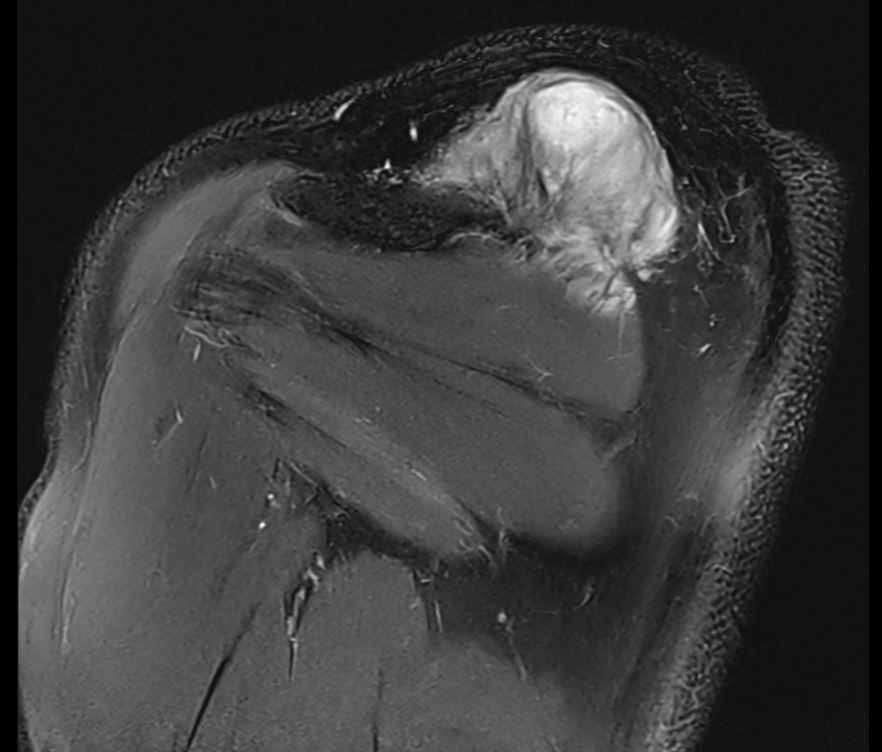

MRI

Soft tissue mass